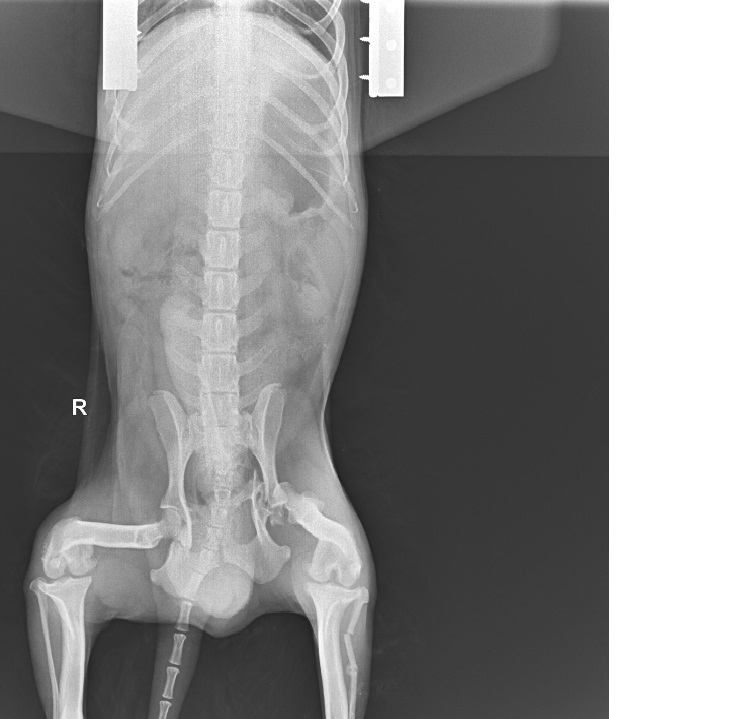

Ma to poprawić komfort życia bez bólu - i ruchomość kończyny - miednica jest tak popękana że niestety bez operacji nie będzie miał komfortowego życia. Postaram się wrzucić zdjęcia z RTG i opis konsultacji wczoraj już nie dałam rady. -

Kochani mamy dobre wieści, nawet bardzo dobre! Okazało się że tego pęknięcia kręgosłupa nie trzeba operować, doktor Bissenik obejrzał malucha, zrobił rtg ale zdjęcia wyszły bardzo kiepsko ponieważ kończynę miedniczną podwijał Tobi pod siebie - pewnie mu tak wygodniej było i mniej bolalo. Doktor znieczulił naszego chłopca i zrobiliśmy RTG w znieczuleniu - okazało się że ta miednica jest w bardzo kiepskim stanie a operacja powinna być wykonana do 3 dni po urazie a my dokładnie nie wiemy kiedy uraz nastąpił i napewno minęło sporo czasu od zdarzenia. Doktor powiedział że kość jest tak roztrzaskana i zgruchotana ( jest tam gruz ) że nie podejmie się w chwili obecnej operacji bo mógłby wyrządzić więcej szkody niż pożytku. Odłamki nie są na tyle duże aby mieć pewność że usunie się wszystkie. Aby zachować ruchomość stawu ( bo już w miednicy zaczęły się zrosty kości ) - jedyna możliwość to poczekać 4 tyg aż samo się troszkę podgoi i wykonamy zabieg resekcji główki kości udowej. Pozatym kręgosłupem mamy się nie przejmować bo zdarzyło się to w części bezrdzeniowej - Doktor powiedział że stan Tobiego nie jest zły - że będzie normalnie chodził po tej operacji. Narazie mamy zalecenie 4 tyg bezwzględnego klatkowania w kennelu tak aby ruch był ograniczony + dostaliśmy lek przeciwbólowy na 10 dni. Mamy się zgłosić za 4 tyg i umówić termin zabiegu. Korzystając z okazji że Tobi był w znieczuleniu poprosiłyśmy z Dorotą o podgolenie mu troszkę tyłka z sierści aby łatwiej było zachować higienę. On ma strasznie dużo kołtunów, zmechaconej sierści - jak wydobrzeje napewno trzeba będzie go podciąć aby piękna nowa sierść odrosła - ale to już w przyszłości :) Mamy też spory problem ponieważ miejsce w którym Tobi teraz przebywa - jest tymczasowe. Nie może tam długo zostać i tu pojawia się pytanie i zarazem prośba czy ktoś znalazłby kawałek kąta w domu aby Tobiego do i po operacji " przetrzymać " w klatce kennelowej ? Zapewniamy oczywiście karmę i usługi weterynaryjne - szukamy ciepłego, sprawdzonego miejsca. On jest totalnie bezproblemowy jeśli chodzi o " obsługę " - grzeczny, spokojny i cichutki jakby go nie było. Cudny pies, w gabinecie dał ze sobą zrobić wszystko, dosłownie wszystko... Prosimy pomyślcie, popytajcie...może ktoś się zgodzi zaopiekować Tobim I teraz ta mniej przyjemna rzecz - finanse... Za konsultację zapłaciłyśmy dzisiaj 237 zł Szacowany koszt operacji to 900-1000zł Za chwilkę wkleję zdjęcia i filmiki jakie nagrywała Dorota :) Bardzo bardzo bardzo jej dziękuję za dziś :******* i za obecność i wsparcie bo byłyśmy mega zestresowane -